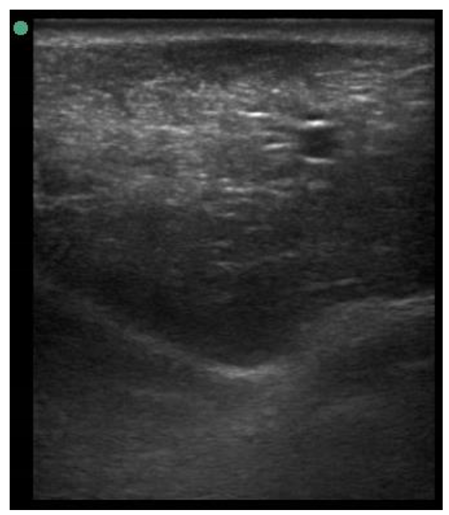

| 113 days of pregnancy (P113) Scanning depth 4.7 cm | ![]() | ![]() | MT generous: 28.9 mm MT conservative: 25.9 mm Gland cistern: 3.3 mm Parenchyma: 10.9 mm Fat Pad: 10.0 mm |